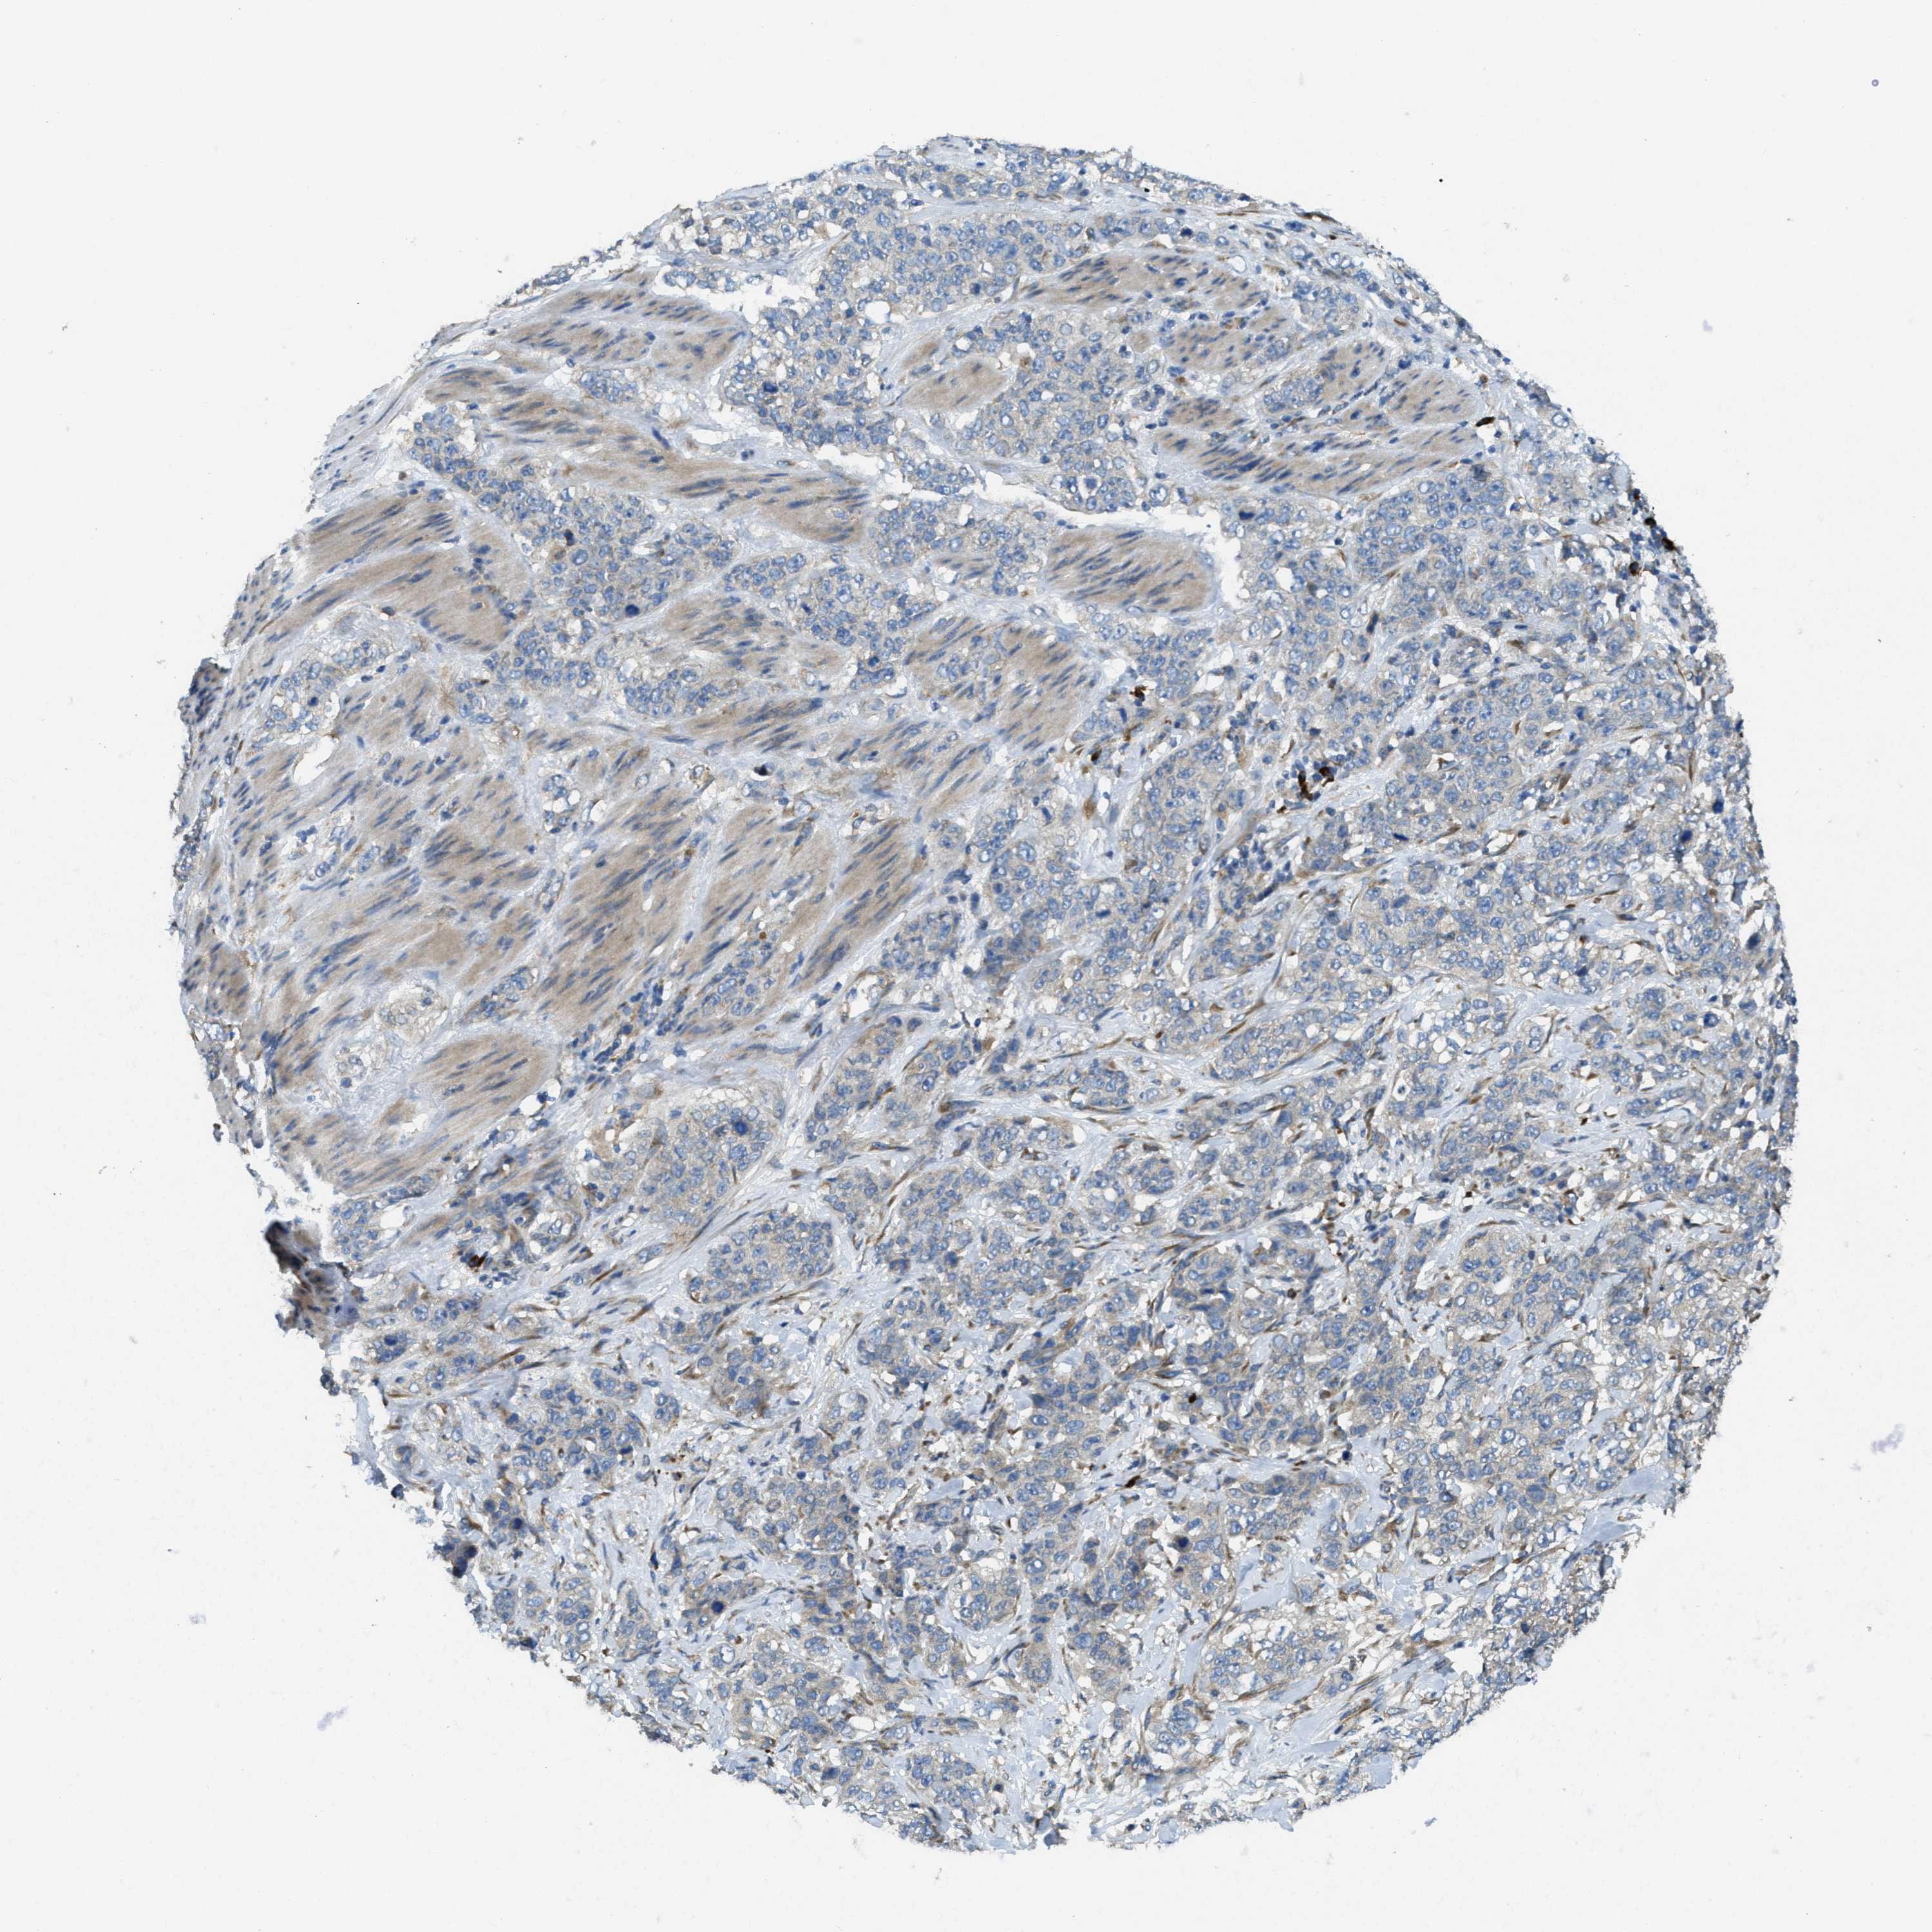

STOMACH CANCER - Protein expressioni

A mouse-over function shows sample information and annotation data. Click on an image to view it in a full screen mode. Samples can be filtered based on level of antibody staining by selecting one or several of the following categories: high, medium, low and not detected. The assay and annotation is described here.

Note that samples used for immunohistochemistry by the Human Protein Atlas do not correspond to samples in the TCGA dataset.

Antibody stainingi

Antibody staining in the annotated cell types in the current human tissue is reported as not detected, low, medium, or high, based on conventional immunohistochemistry profiling in selected tissues. This score is based on the combination of the staining intensity and fraction of stained cells.

Each image is clickable and will lead to virtual microscopy that enables deeper exploration of all samples and also displays staining intensity scores, fraction scores and subcellular localization as well as patient and tissue information for each sample.

Antibody HPA011276

Antibody HPA017062

Staining

High

Medium

Low

Not detected

Intensity

Strong

Moderate

Weak

Negative

Quantity

>75%

75%-25%

<25%

None

Location

Nuclear

Cytoplasmic/membranous

Cytoplasmic/membranous,nuclear

Adenocarcinoma, NOS

Adenocarcinoma, High grade